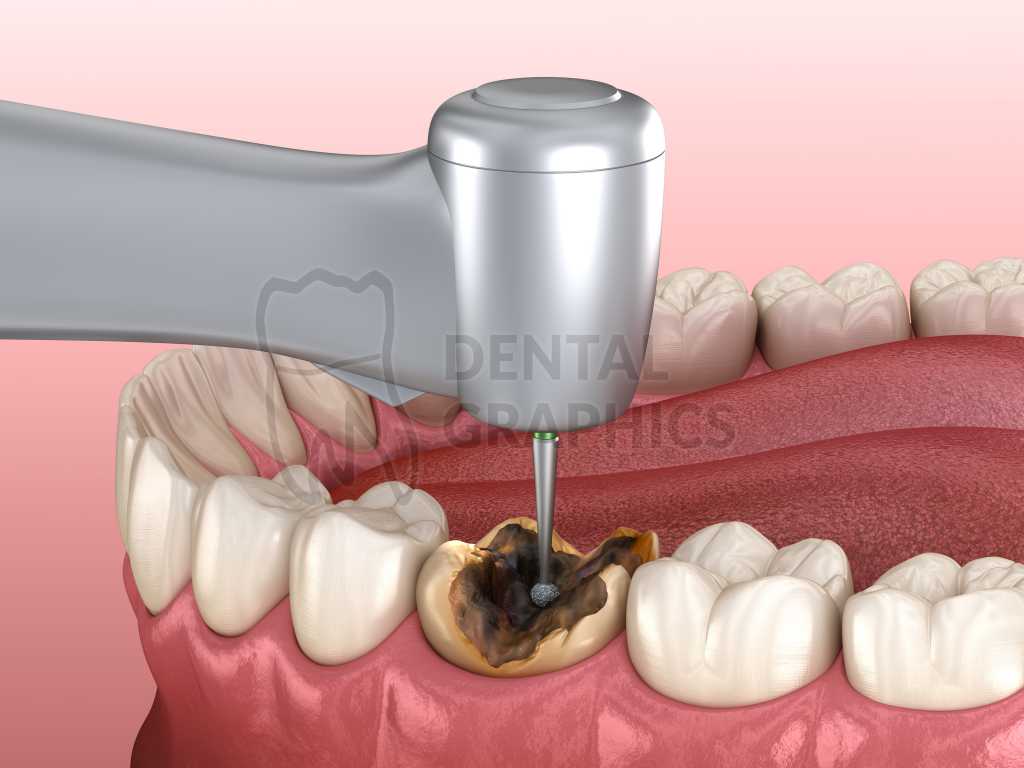

Что делать, если откололся кусок зуба: советы и рекомендации

Раздел: Необычные решения